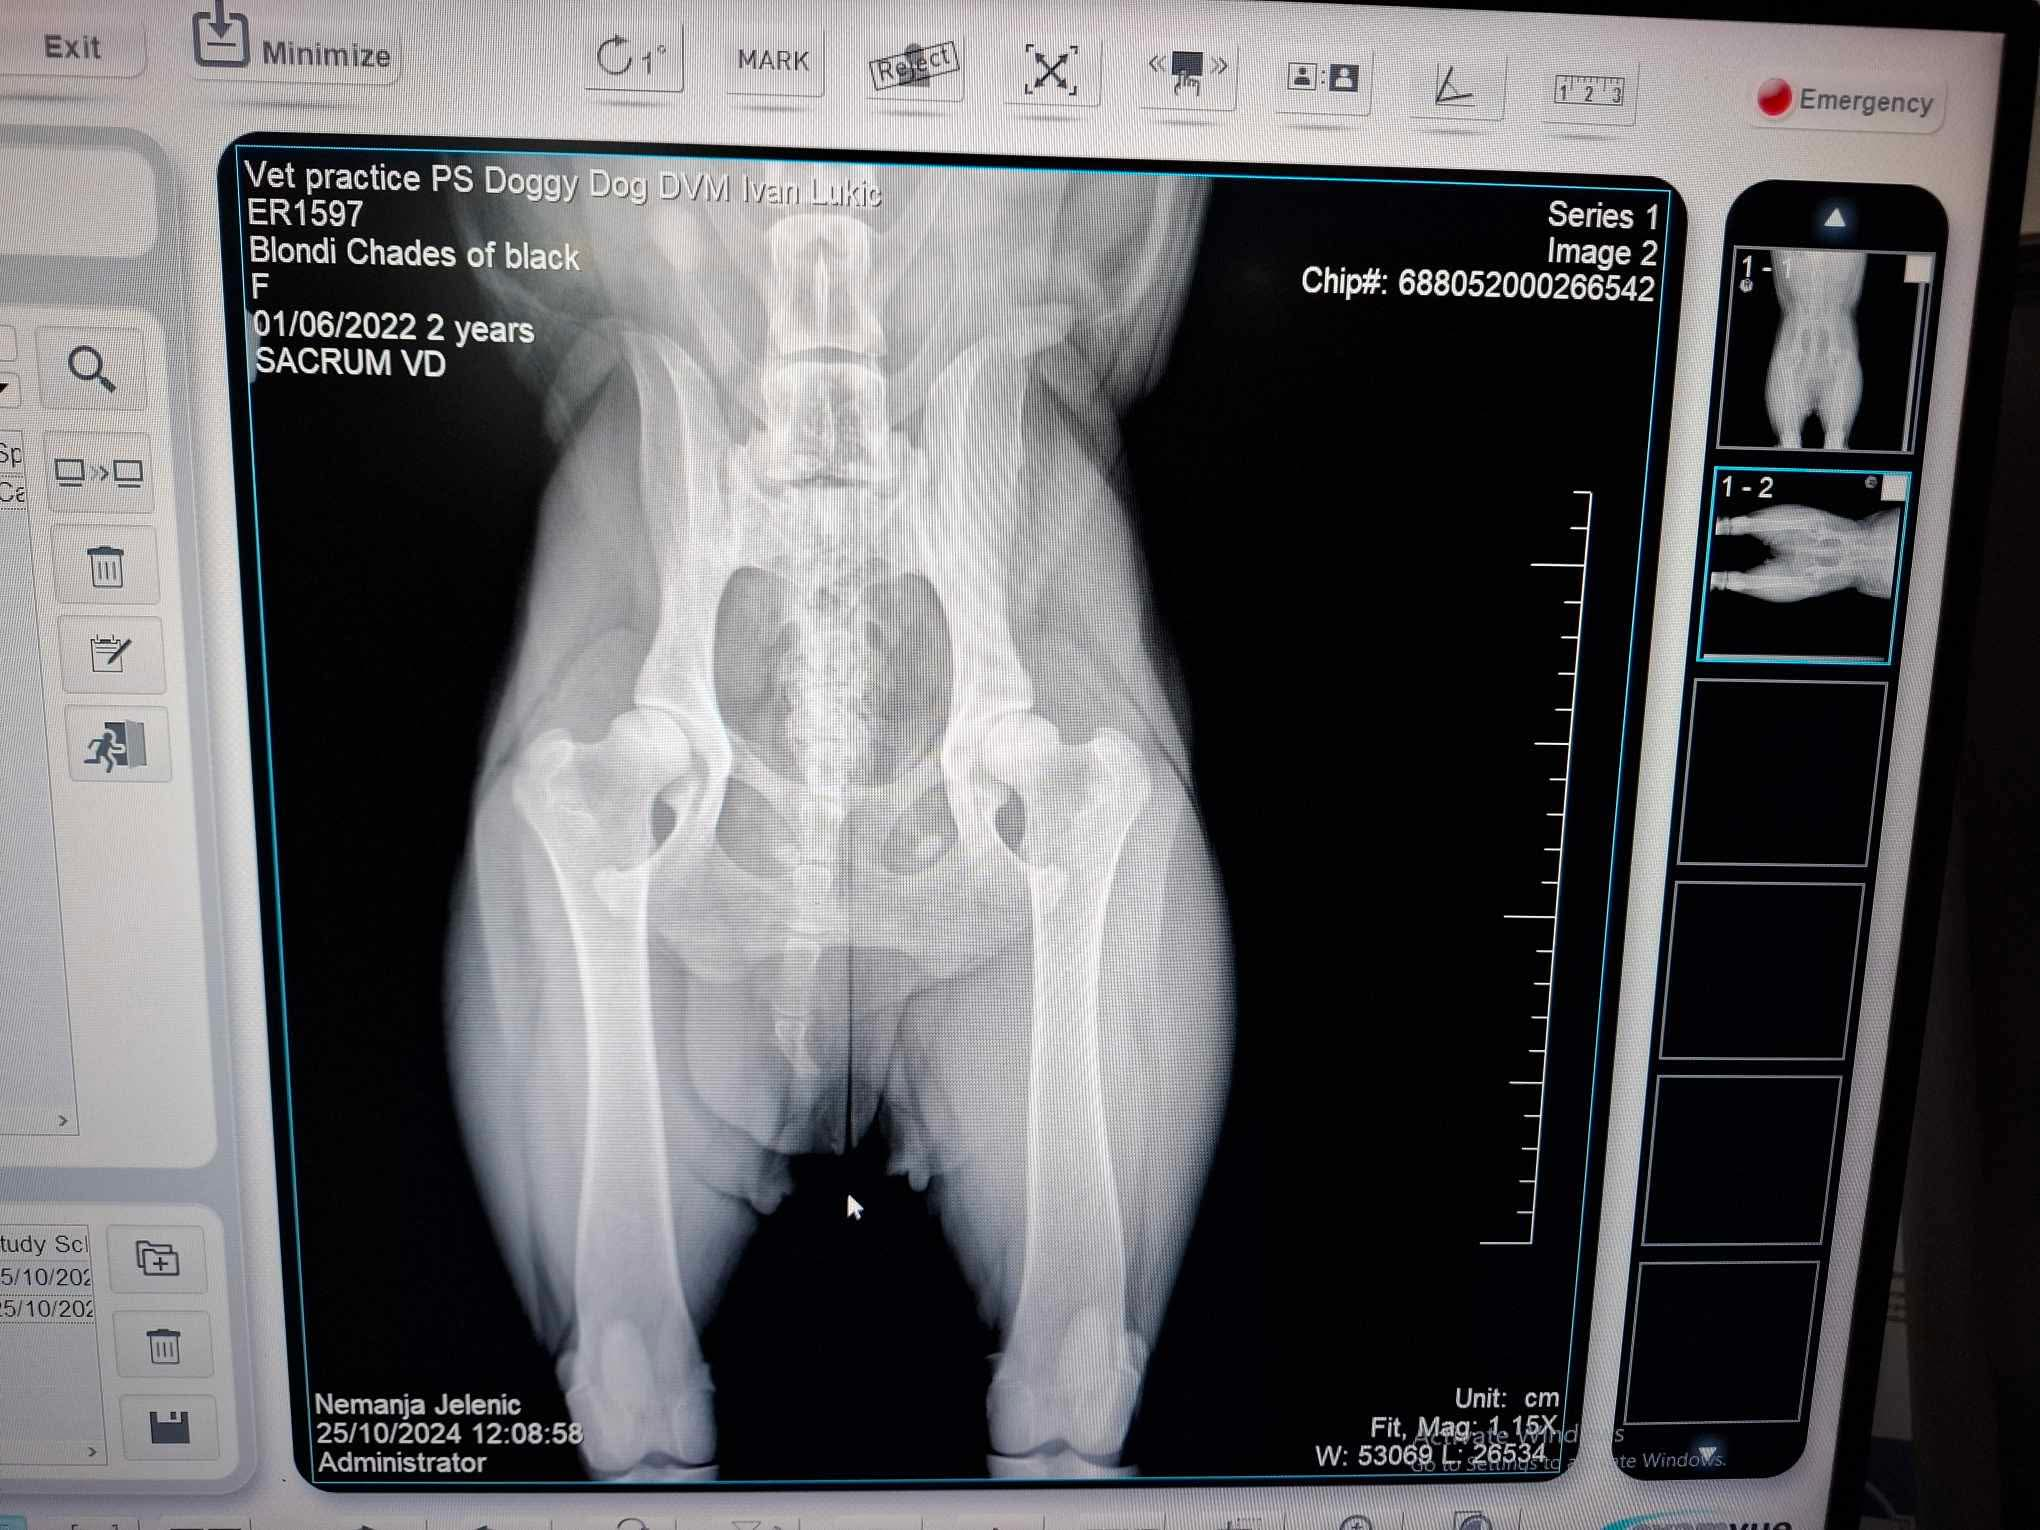

Documents For health testing

Health testing